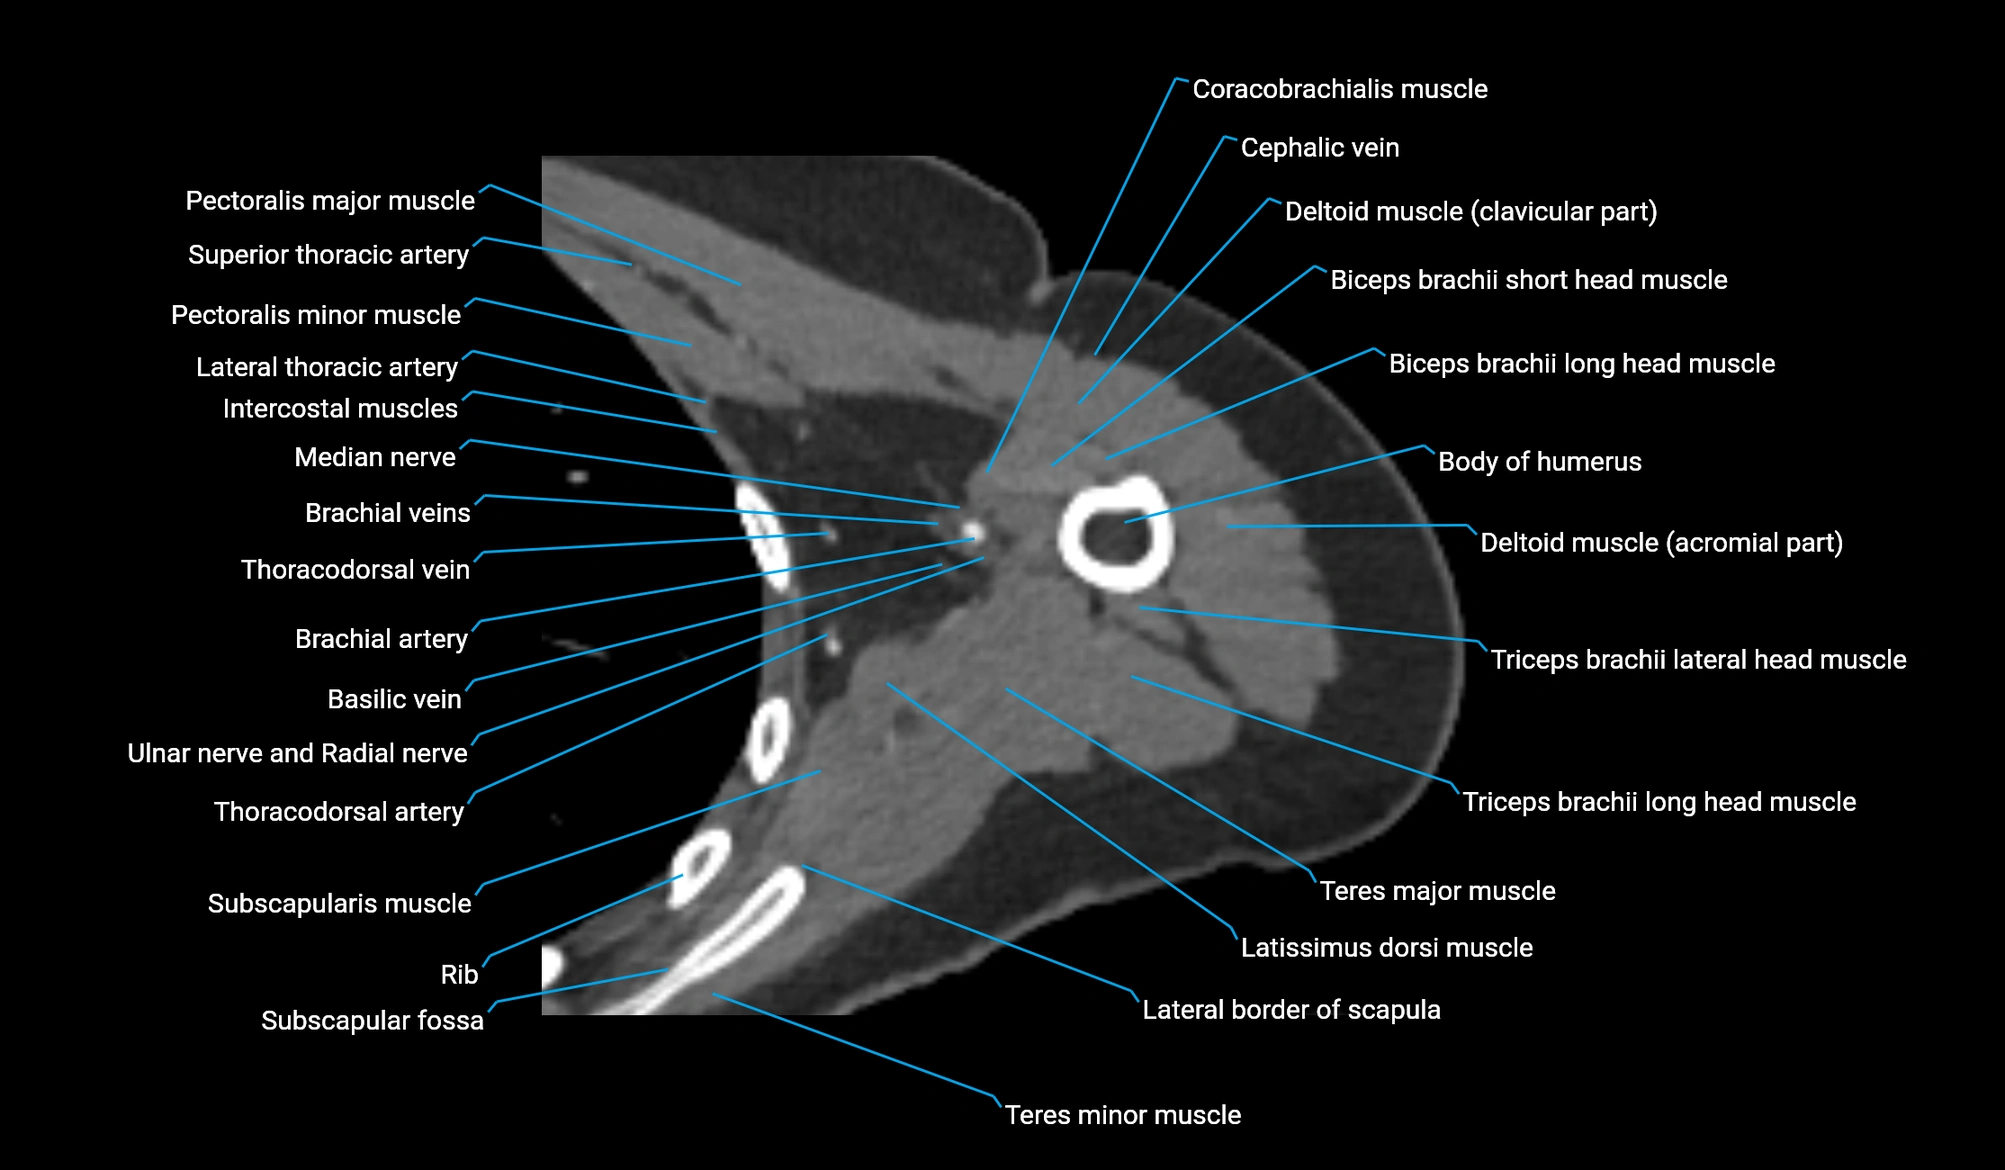

CT image